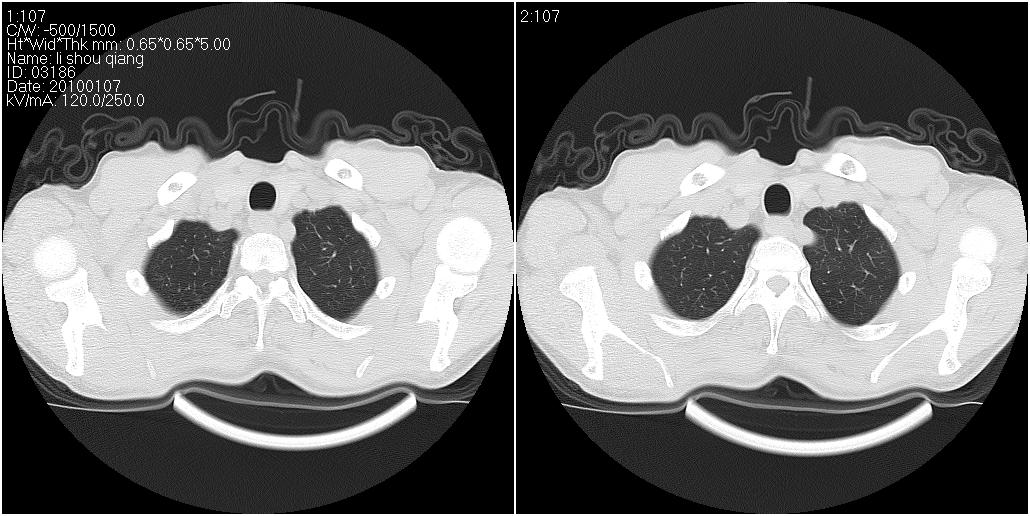

标题: CT24038:男性,58岁。主因咳嗽带血性CT检查。 [打印本页]

标题: CT24038:男性,58岁。主因咳嗽带血性CT检查。

右肺中叶外侧段见一不规则的软组织肿块,边缘可见毛刺,并见厚壁空洞,与胸膜分界欠清。另左下肺见多个小囊状扩张区